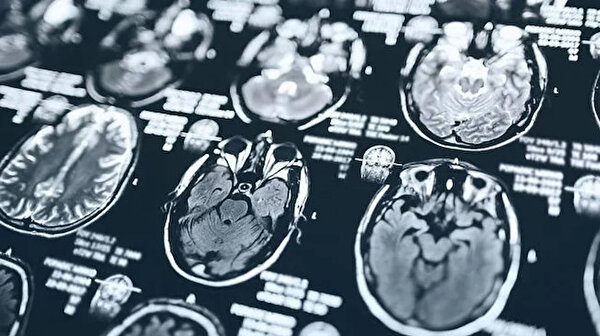

MRI taramaları analiz edildi

Bellek, duygu, dikkat ve dil gibi daha yüksek bilişsel işlevlerde rol oynayanlar da dahil olmak üzere, korteksteki bölgelerin yüzey alanı ve kalınlığını incelemek için MRI taramaları analiz edildi. Taramalar ayrıca, kan akışındaki değişikliklerin beyin aktivitesini gösterdiği beynin farklı bölgeleri arasındaki bağlantıları da analiz etti.

Araştırma, sosyoekonomik dengesizlikler ve yoksunluk gibi toplumsal eşitsizliğin daha yüksek olduğu bölgelerde yaşayan çocukların, beyin korteksinin yüzey alanının küçülmesi ve beynin çeşitli bölgeleri arasındaki bağlantıların değişmesiyle bağlantılı olduğunu buldu.